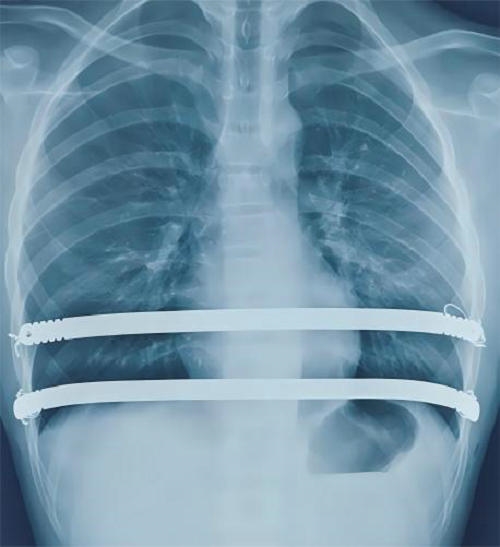

微创漏斗胸矫形术是在胸腔镜辅助下,将术前特制的Nuss钢板术中经规划的肋间,于胸骨后心包前置放在合适位置,进行钢板翻转,将胸骨抬举达到矫形的目的。矫形效果立竿见影。通常仅需双侧腋下两个小切口即可完成手术。术后要注意避免弯腰等不当动作,注意有无钢板移位的问题。对于无特殊情况的接受手术的患者一般术后2-4年拆除钢板。同时要重视术后心理辅导、康复训练及呼吸锻炼等,有助于畸形的矫正及心肺功能的康复。

钢板翻转矫形